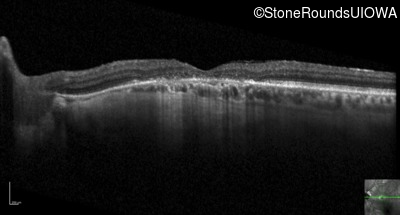

Optical Coherence Tomography - Left - 20/200 +1

Exemplar / OCT Stack

OCT Stack